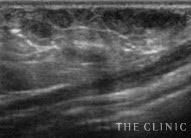

吸引・除去後   しこりの消失を確認